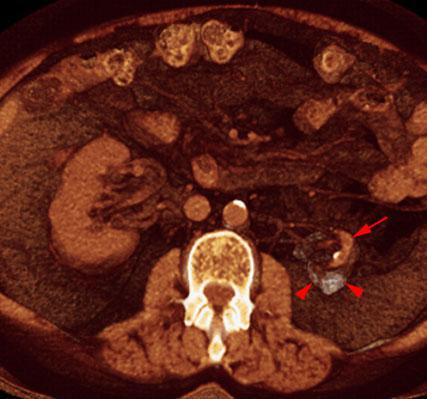

Riñón mastic

VR seccional. Visión axial caudal. Estudio no contrastado. Atrofia renal izquierda (flecha) con riñón derecho compensador. Calcificación parcial del parenquima renal (puntas de flecha)